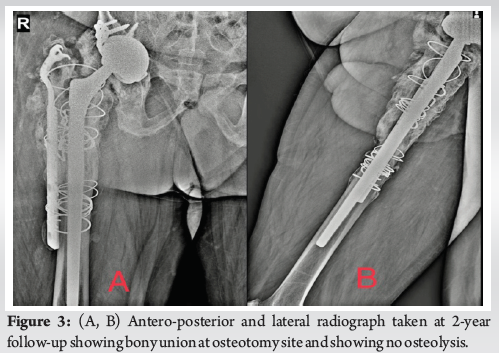

Case Report: Total Knee Arthroplasty in Ipsilateral Below-Knee Amputee

Christopher E Marrero , Jonathan Willard ………………………………p.07-12